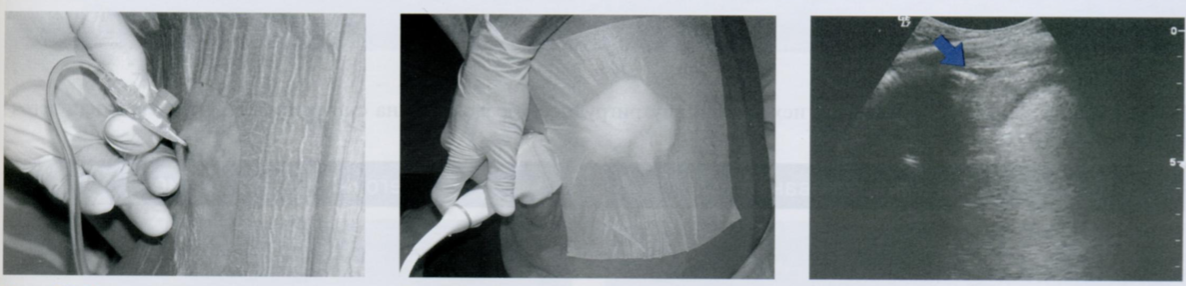

Кожа обрабатывается антисептиком, под ультразвуковым контролем выбирается оптимальное место введения иглы, которое отмечается шариковой ручкой по верхнему краю ребра (маркер уж очень орошо стирается при обработке антисептиком).

После того, как мосто пункции обложено стерильной салфеткой с отверстием и повторно обработано антисептиком, тонкой иглой прокалывают кожу, вводят анестетик с образованием «лимонной корки».

Иглу продвигают вперед, до париетальной плевры, по ходу инфильтрируя ткани (стрелки) анестетиком, пока не начнет аспирироваться плевральный выпот (обычно желтоватый). Далее убираем тонкую иглу.

Во время введения иглы врач фиксирует средний и безымянный пальцы недоминирующей руки к грудной клетке, чтобы введение иглы было медленным и максимально контролируемым.